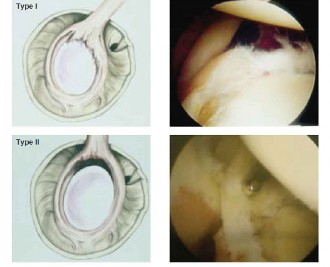

An MR arthrogram shows the superior labrum is detached from the superior glenoid, and the biceps tendon anchor is disrupted. How would this tear be classified according to the Snyder classification?

The correct answer is (B). The Snyder classification of SLAP tears is the first widely used classification systems for SLAP tears and consists of types I to IV (see Fig. 2–22A–B and Table 2–3). In type I tears (Answer A), there is fraying of the glenoid edge of the superior labrum, but the biceps tendon and superior labrum are both firmly attached to the biceps anchor and glenoid edge. In type II tears (Answer B), the biceps tendon and the superior labrum are detached from the superior glenoid edge and biceps anchor. In type III tears (Answer C), there is a bucket-handle tear of the superior labrum, but the remainder of the superior labrum and biceps tendon remain firmly attached to the glenoid rim and biceps anchor. In type IV tears (Answer D), there is a bucket-handle tear of the superior labrum that extends into the biceps tendon with extension of parts of the labral flap or biceps tendon into the joint space, and the remainder of the labrum and biceps tendon remain firmly attached to the glenoid rim and biceps anchor. Type V tears (Answer

E) do not exist. Complex lesions do exist and typically consist of a combination of type II and IV tears.

Figure 2–22(A–B) Snyder classification of rotator cuff tears in cartoon and arthroscopic views. (From Mileski RA, Snyder SJ. Superior labral lesions in the shoulder: pathoanatomy and surgical management. J Am Acad Orthop Surg. 1998;6(2):121–131.)

| ### Table 2–3 SNYDER CLASSIFICATION DESCRIPTION AND TREATMENT Snyder Classification | Description of Labrum | Description of Biceps Tendon | Treatment |

| --- | --- | --- | --- |

| Type I | Fraying of glenoid edge | Intact | Labrum debridement |

| Type II | Detached from glenoid | Detached from anchor | Labrum repair if unstable and <25–30 y/o |

Biceps tenodesis if unstable and >30–35 y/o Labrum debridement if degenerative at any

Type III

| Bucket-handle tear

| Intact

| age

Labrum debridement with MGHL repair if detached

| ---|---|---|---|

Type IV

| Bucket-handle tear

| Tear extends into biceps

| If young or old and <30% biceps torn, labrum and biceps debridement

If young and >30% biceps torn, labrum repair and biceps tenodesis/tenotomy

If old and >30% biceps torn, labrum debridement and biceps tenodesis/tenotomy

From Mileski RA, Snyder SJ. Superior labral lesions in the shoulder: pathoanatomy and surgical management. J Am Acad Orthop Surg.(1998);6(2):121–131.